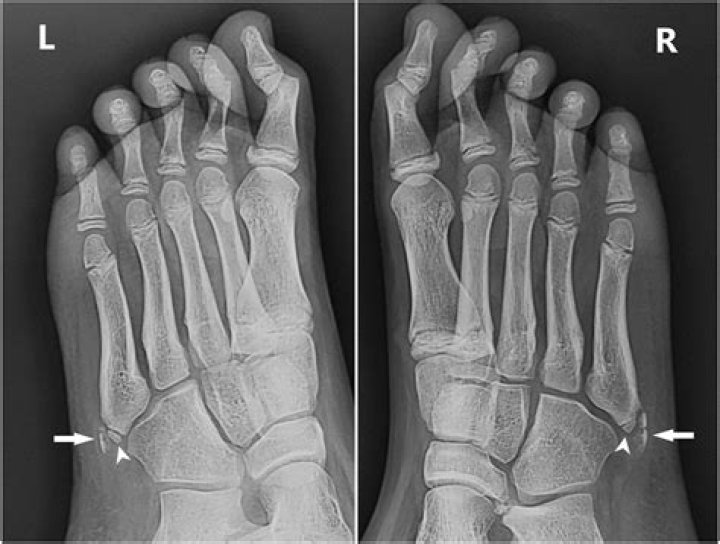

Is there a growth plate at the base of the 5th metatarsal?

What age does 5th metatarsal apophysis fuse?

Apophysis of the fifth metatarsal base appears on radiographs at age 10 for girls, and age 12 for boys. Fusion of the apophysis and the fifth metatarsal base usually takes place within the following 2–4 years.

Iselin’s Disease is a common acquired condition cause by traction apophysitis of the the peroneus brevis tendon at the tuberosity of the fifth metatarsal in children and presents with lateral foot pain.

Iselin disease is painful inflammation of the apophysis (growth plate) at the base of the 5th metatarsal (foot bone). The growth plate is made up of cartilage, which is softer and more vulnerable to injury than mature bone.